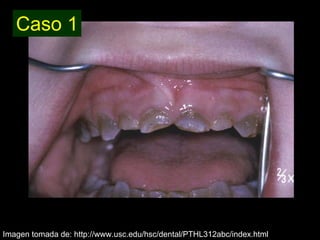

Dentinogénesis imperfecta es una condición genética que causa un disturbio en la formación de la dentina. Existen tres tipos principales. El tipo I se asocia con osteogénesis imperfecta. El tipo II solo afecta la dentina y causa dientes amarillos o grises con atrición. El tipo III es raro y se encuentra en un área aislada de Maryland, con exposiciones pulpares frecuentes. Todos los tipos muestran características radiográficas como obliteración de cámaras y conductos,